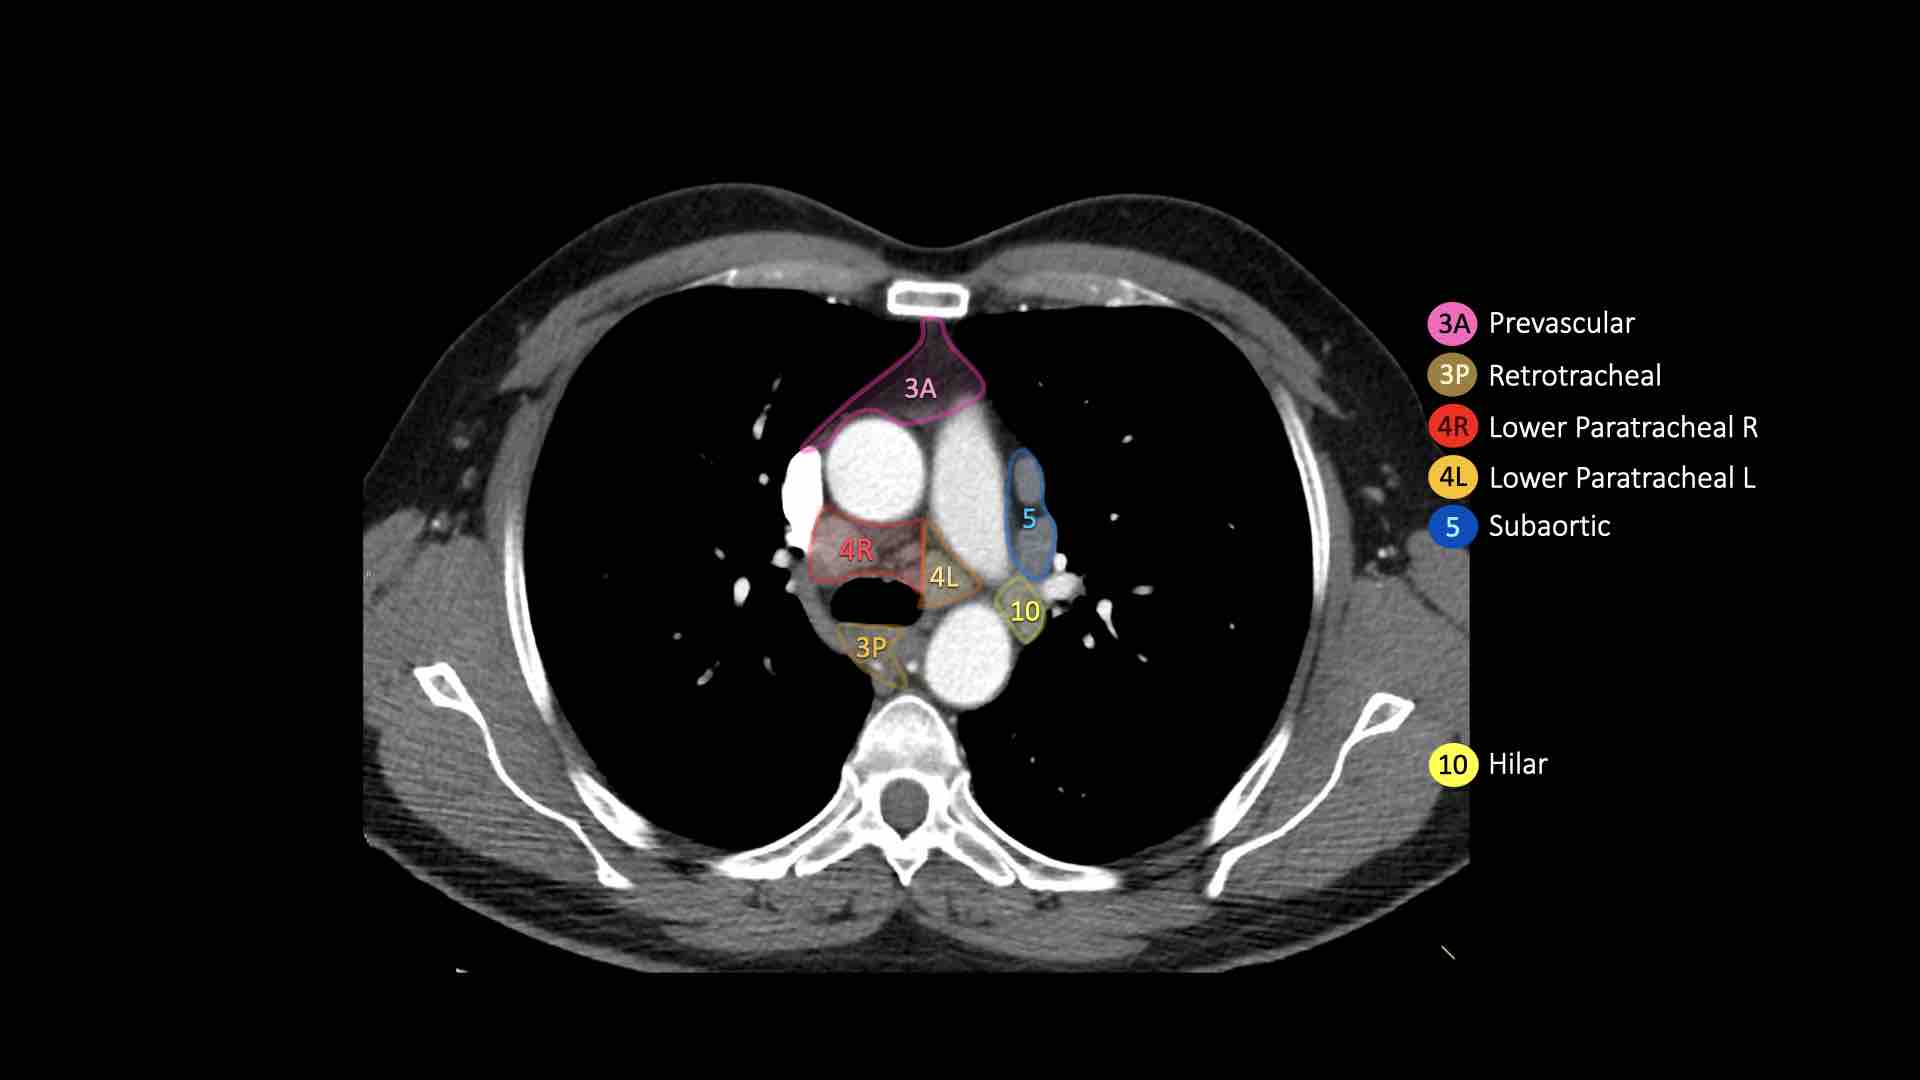

3A.Trước mạch máu

Các hạch này không tiếp giáp với khí quản như các hạch ở nhóm 2, mà nằm ở phía trước các mạch máu.

3P.Trước cột sống

Các hạch không tiếp giáp với khí quản như các hạch ở nhóm 2, mà nằm sau thực quản, tức là ở vị trí trước cột sống.

4R.Cạnh khí quản dưới

Từ điểm giao nhau giữa bờ dưới tĩnh mạch vô danh (tĩnh mạch tay đầu trái) với khí quản đến bờ dưới tĩnh mạch đơn.

Hạch nhóm 4R trải dài từ bờ bên phải đến bờ bên trái của khí quản.

4L.Cạnh khí quản dưới

Từ bờ trên của quai động mạch chủ đến bờ trên của động mạch phổi trái.

5. Dưới động mạch chủ

Các hạch này nằm trong cửa sổ phế động mạch (AP window), ở phía ngoài dây chằng động mạch.

Các hạch này không nằm giữa động mạch chủ và thân động mạch phổi mà nằm ở phía ngoài các mạch máu này.

10. Hạch rốn phổi

Bao gồm các hạch tiếp giáp với phế quản gốc và các mạch máu rốn phổi.

Bên phải, trải dài từ bờ dưới tĩnh mạch đơn đến vùng gian thùy.

Bên trái, từ bờ trên động mạch phổi đến vùng gian thùy.

Bên trái là hình ảnh ngay trên mức thân động mạch phổi, cho thấy các hạch cạnh khí quản dưới bên trái và bên phải.

Ngoài ra còn có các hạch nhóm 3 và nhóm 5.

Bên trái là hình ảnh ở mức phần dưới khí quản, ngay trên carina.

Bên trái khí quản là các hạch 4L.

Lưu ý rằng các hạch 4L này nằm giữa thân động mạch phổi và động mạch chủ, nhưng không nằm trong cửa sổ phế động mạch, vì chúng nằm ở phía trong dây chằng động mạch.

Hạch nằm bên ngoài thân động mạch phổi là hạch nhóm 5.